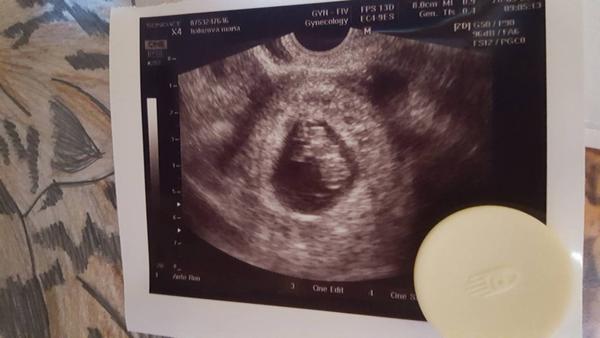

My sme boli na MESA TESE a našli nám a už máme aj po vklade a vyšlo nám tehotenstvo po 6 dnoch od oplodnenia som skúsila test a vyšiel duch potom na 10 den sme boli na krv a potvrdili tehotenstvo HCG v krvi som mala 100 a po 4-5 dnoch som mala hcg 490 tak nám sa to podarilo na prvý krát teda dúfam lebo sme mali tú poslednú krv na hcg v polovici augusta a na prvú kontrolu idem na budúci týžden 28.9